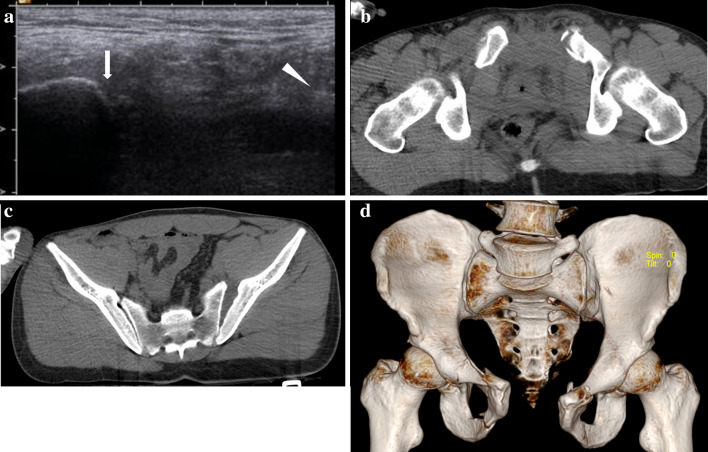

Fig. 3.

a US shows pubic symphysis widening; the distance between the two pubic tubercles (arrows) is < 2.5 cm. b CT confirms the diastasis of the pubic branches, less than 2.5 cm

Fig. 4.

a US shows large diastasis of the pubic symphysis, greater than 2.5 cm. The right pubic branch is clearly visible (arrow), while only a detached fragment of the left branch is visible (arrowhead): b, c axial CT scan and d 3D reconstruction confirm the large widening of the pubic symphysis and the ‘open book’ fracture of the pelvis

The analysis carried out to assess the degree of agreement between FAST–PLUS and CT showed 5/67 patients (7.5%) with a critical pubic SW (> 2.5 cm in transverse diameter) suggestive of unstable OB pelvic fracture and 62/67 (92.5%) without any signs of SW at FAST–PLUS. At CT, findings of unstable OB pelvic fracture were confirmed in all patients with positive results at FAST–PLUS. Similarly, all patients with negative results for critical pubic SW (< 2.5 cm in transverse diameter) at FAST–PLUS were found to be negative at CT exam too (Figs. 2, 3, 4). The level of correlation between the two methods was high (Kappa value = 1).